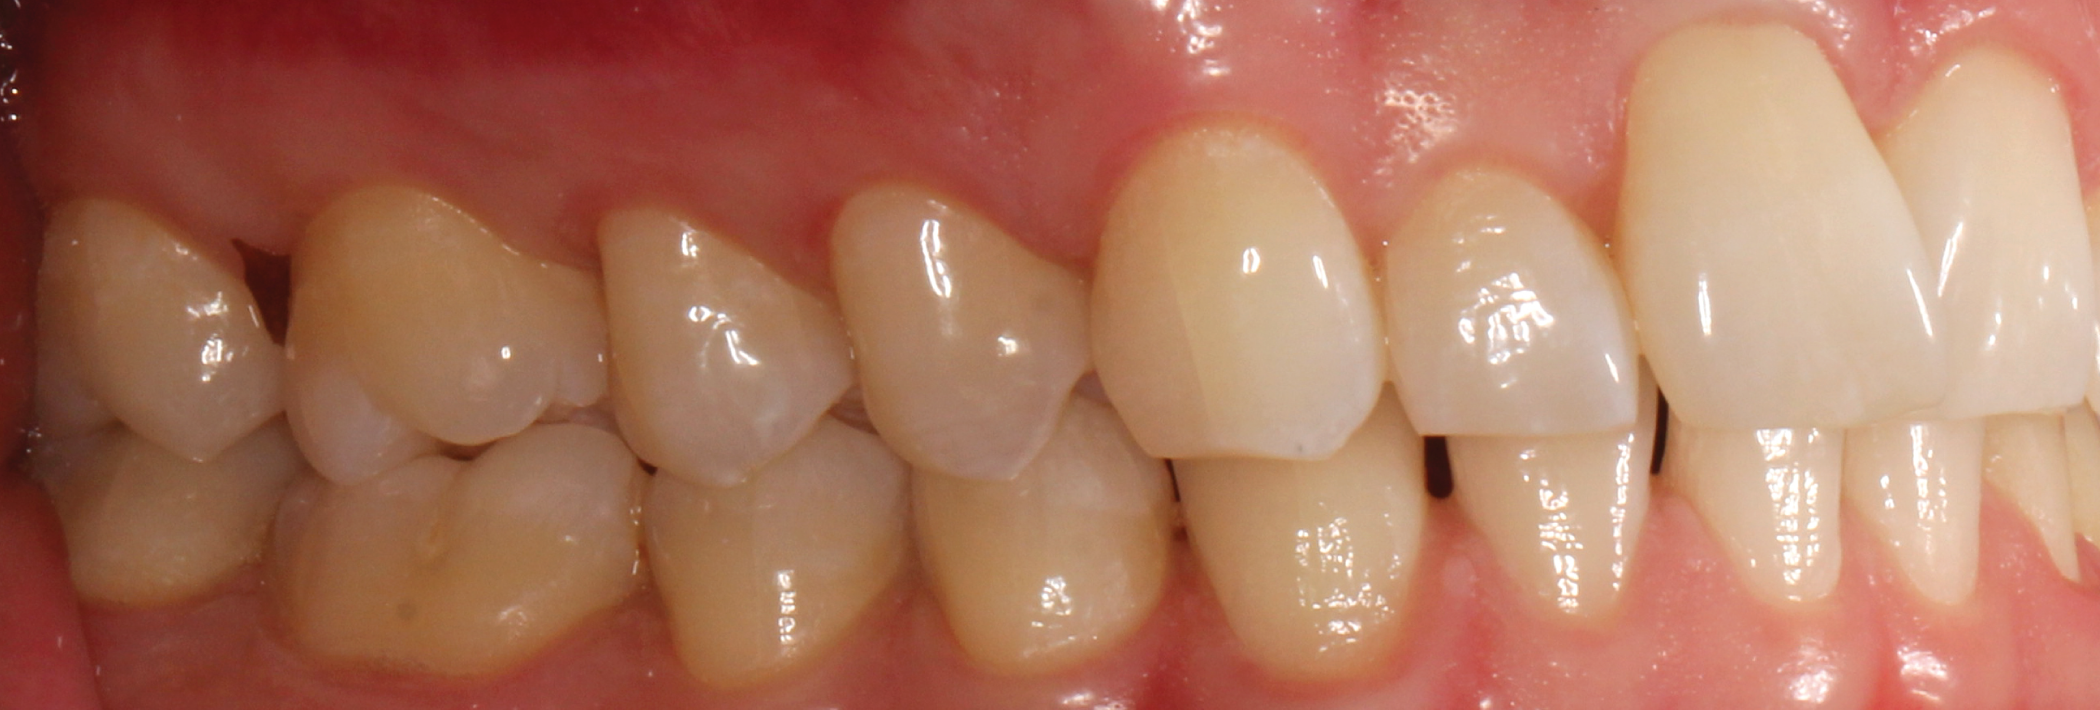

Fig. 7: Pre-op (right lateral view) Fig. 8: Pre-op (left lateral view)